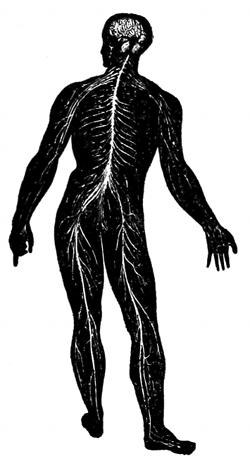

Nerves.

—Nerves are divided into two general classes,

called medullary and non-medullary nerves. The non-medullated

type arise mostly from the sympathetic system,

while the medullated type arise from the brain and